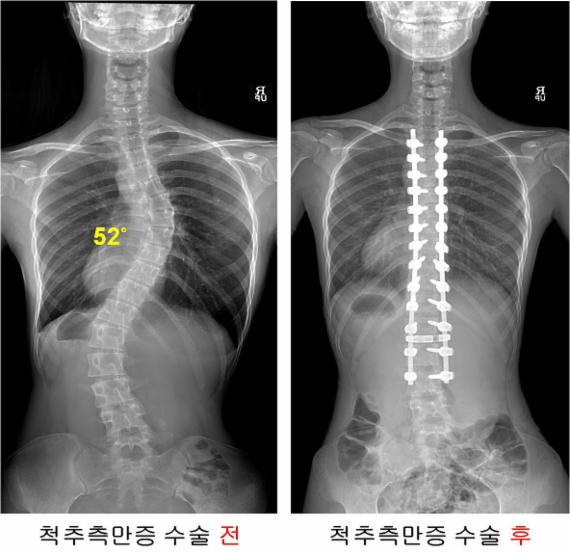

¼­¿ï¾Æ»êº´¿øÀÌ 1990³â ÃÖÃÊ Ã´ÃßÃø¸¸Áõ ¼ö¼ú¿¡ ¼º°øÇÑ ÀÌ·¡ Áö±Ý±îÁö 1000·Ê ÀÌ»ó ¼ö¼ú ±â·ÏÀ» ´Þ¼ºÇß´Ù. ¼ö¼ú¹ÞÀº ȯÀÚ Áß ´Ü ÇÑ ¸íµµ ¸¶ºñ°¡ ¹ß»ýÇÏÁö ¾Ê¾Æ Ãø¸¸Áõ ¼ö¼úÀÇ ¾È¼±¼º±îÁö ÀÔÁõÇß´Ù´Â Æò°¡´Ù.

¼­¿ï¾Æ»êº´¿ø ôÃßÃø¸¸Áõ¼¾ÅÍ ÀÌÃἺ ±³¼öÆÀÀº Áö³­ 1990³â 16»ì ¿©ÀÚ¾ÆÀÌ¿¡°Ô SÀÚ ÇüÅ·Π±¸ºÎ·¯Áø ôÃ߸¦ ¹Ù·Î ¼¼¿öÁִ ôÃßÃø¸¸Áõ ¼ö¼úÀ» ÃÖÃÊ ½ÃÇàÇß´Ù.

ôÃß°¡ ÀÏÀÚ·Î ¼­ ÀÖÁö ¾Ê°í ¿·À¸·Î ÈÖ¾îÁø Ãø¸¸ÁõÀÇ ¾à 90%´Â ±× ¿øÀÎÀ» Àß ¸ð¸£´Â Ư¹ß¼º Ãø¸¸ÁõÀÌ´Ù. ¾î·ÈÀ» ¶§´Â Àß ¸ð¸£´Ù°¡ 10´ë ÃÊ¹Ý ¿©Çлý¿¡¼­ ¸¹ÀÌ ¹ß°ßµÇ´Â Ư¡À» Áö³æ´Ù. º¸Åë 45~50¡Æ ÀÌ»ó ±â¿ï¾îÁö¸é ¼ö¼úÀ» ½ÃÇàÇÑ´Ù.

¶ÇÇÑ ¼ö¼ú Àü ôÃßÀÇ ÈÖ¾îÁø Á¤µµ¸¦ ³ªÅ¸³»´Â °¢µµ°¡ Æò±Õ 57.3¡Æ¿´Áö¸¸, ¼ö¼ú ÈÄ¿¡´Â 11.9¡Æ±îÁö ÆìÁ® ¾à 79%ÀÇ ±³Á¤À²À» º¸ÀÌ¸ç ¼¼°èÀûÀÎ ¼öÁØÀÇ ¼ö¼ú È¿°ú¸¦ º¸¿´´Ù.

ƯÈ÷ 1000·ÊÀÇ ¼ö¼úµ¿¾È ½Å°æ¼Õ»ó ȯÀÚ°¡ ´Ü ÇÑ ¸íµµ ¹ß»ýÇÏÁö ¾ÊÀº °á°ú·Î ³ªÅ¸³µ´Ù.